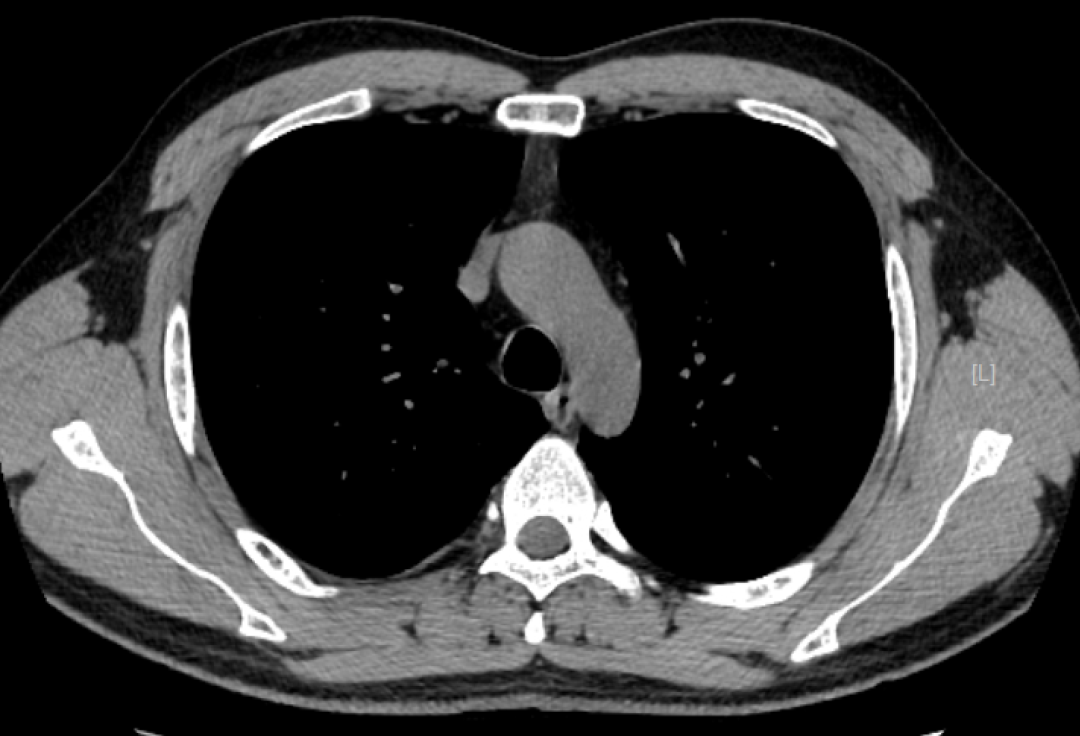

CT检查成像原理与DR类似,使用的是X射线,之后通过计算机成像。相较DR,CT可以多角度、多层面、多功能扫描成像,就像把一个面包切成多个平面进行观察。

检查应用范围:从头到脚,均可进行CT平扫,主要运用于头颅、颈部、胸部、腹部、脊柱、盆腔、四肢等部位。特别是高分辨率胸部CT,在检查肺部小结节时,运用非常广泛,CT检查脑出血也有相当的优势,另外微小的骨折、大部分器官的病变都能够看到。

优点:相较DR,CT的密度分辨率更高,可以显示DR检查不能发现或容易遗漏的病变。

注意:部分疾病不能做CT增强检查,如:肝、肾功能不全、甲状腺功能异常、碘对比对剂过敏、重度荨麻疹等,需要CT增强检查的患者需要临床医生评判后才可进行。

而CT检查是把面包切片来看,获得的是真正的断面图像,没有层面以外的结构干扰。虽然细节看的更清楚了,但它就不是一块完整的面包了。